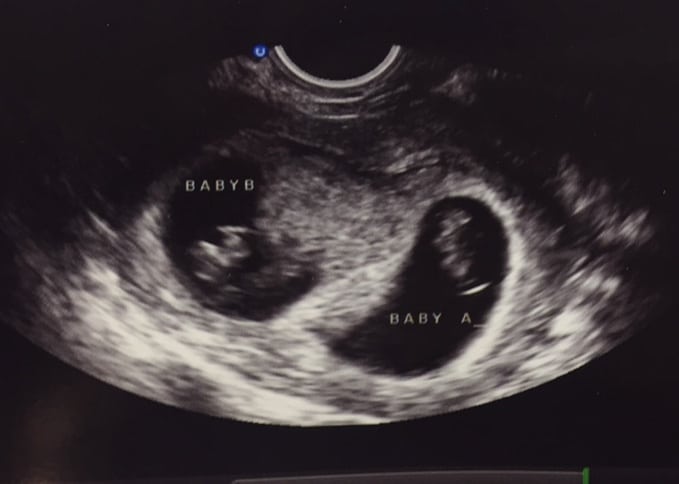

Ultrasound Photos – 8 Week Sonogram

8 week sonogra